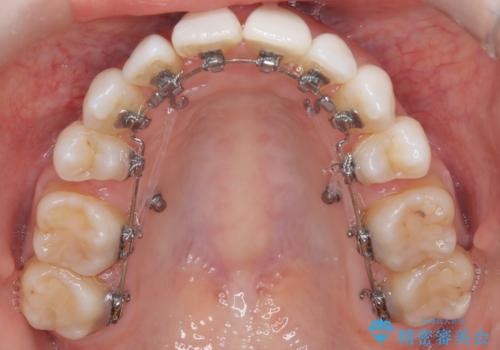

ハーフリンガル矯正|上下4本の抜歯で叢生を改善し、美しい歯並びへ

- 患者様は、歯並びの乱れ(叢生)を整えたいが、前歯の突出感は気にならないとのことで来院されました。診察の結果、全体的な歯列のスペース不足により抜歯が必要と判断。しかし、前歯を大きく下げる必要はなかったため、小臼歯の中でも5番(第二小臼歯)を抜歯する治療計画を立てました。装置は、上顎が舌側(リンガル)、下顎が表側(審美ワイヤー)のハーフリンガル矯正を採用し、目立ちにくさと効率的な歯の移動を両立しました。

抜歯によって歯を並べるためのスペースを確保。その後、ハーフリンガル矯正を用いて、上顎は舌側から、下顎は目立ちにくいワイヤーで歯を誘導し、歯列全体を整えました。治療期間を通じて、噛み合わせのバランスも改善し、機能的にも審美的にも理想的な仕上がりとなりました。患者様からは「目立たずに矯正でき、きれいな歯並びになって嬉しい」とご満足いただきました。